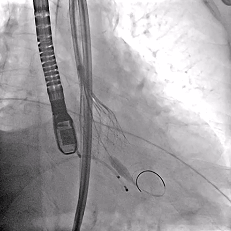

脱钩后造影

瓣膜位置可,无瓣周漏

左冠切线造影,瓣膜同轴性佳,位置可,无瓣周漏